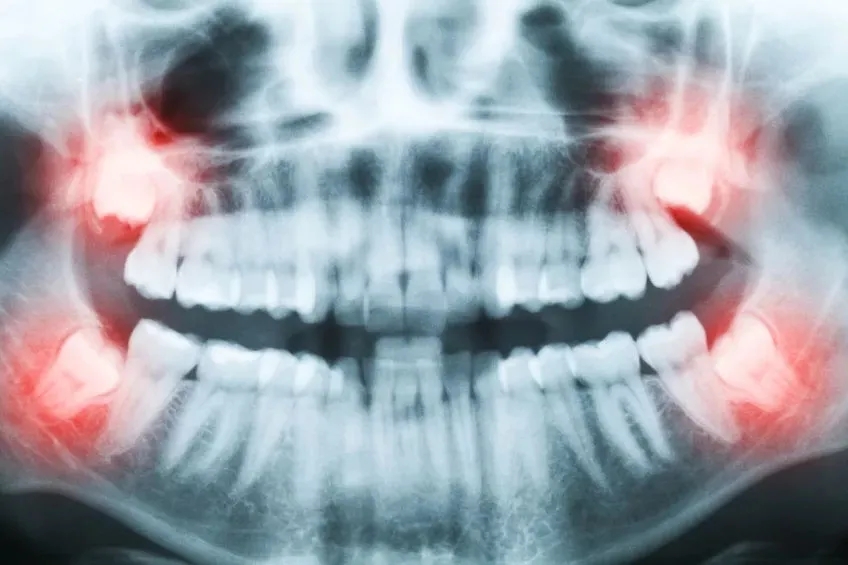

3.智齿

人类在进化过程中吃的食物越来越细,导致颌骨骨量不断减少,使牙齿萌出的位置减少,智齿没有足够的空间生长,所以大多数的智齿长歪,顶着相邻的牙齿,这个地方会出现塞牙,容易造成烂牙!